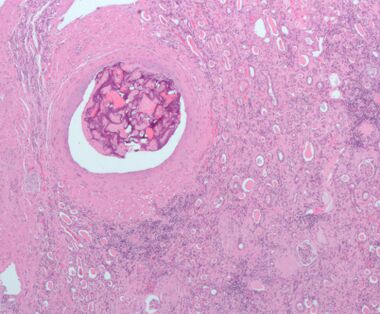

Micrograph of embolic material in the artery of a kidney. The kidney was surgically removed because of cancer. H&E stain. | |

إحداث الانسداد يشير إلى تمرير وإيداع سدادة في تيار الدم. قد تكون مرضية (وفي هذه الحالة تسمى انسداد وعائي)، مثل الانصمام الرئوي، أو علاجية، كإرقاء لعلاج النزيف أو لعلاج بعض أنواع السرطان عن طريق غلق الأوعية الدموية عمدًا لتجويع خلايا الورم.

تتضمن عملية إحداث الانسداد السد الاختياري للأوعية الدموية عن طريق إدخال سدادة، أو بكلمات أخرى غلق وعاء دموي بشكل متعمد.

إن إحداث الانسداد عملية جراحية متدنية الإنتهاك. الغرض هو منه سريان الدم إلى منطقة ما في الجسم، مما يمكن بشكل فعال من تصغير حجم ورم أو غلق أم الدم.